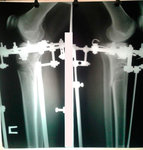

Исходник - 35 лет.

Укорочение правой ноги - 2 см.

Левая голень более деформирована.

Дата операции 22.03.2016г.

Дата снятия аппаратов 22.06.2016г.

Срок лечения 90 дней.

Диагноз: Укорочение правой ноги - 2 см.